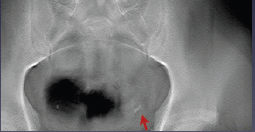

常规腹部平片:

影像描述: X线平片:立位X线腹部平片可疑盆腔内(左侧)点状高密度影,但由于肠道气体影响,双肾影无法显示(患者不愿意接受清洁灌肠)。 断层容积图像:去除了肠道气体的影响,清晰显示盆腔内(左侧)点状高密度影,同时显示左肾中部多发点状高密度影。 断层容积诊断: 左侧输尿管盆内段结石,左肾多发结石。 病例点评: 清洁灌肠,是怀疑泌尿系结石时X线腹部平片检查前的常规准备,许多患者不愿意接受这种暴露,接触敏感部位的检查,清洁灌肠也会给患者带来很大的痛苦。断层容积成像完全不需要清洁灌肠准备。肾结石,输尿管下端结石同时显示,说明断层容积成像能大范围清晰显示病变。